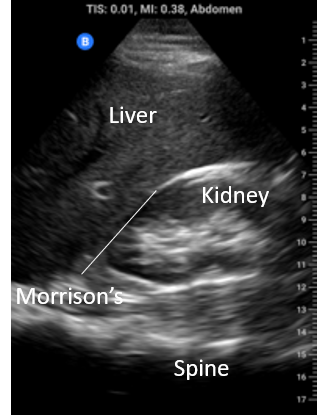

RUQ: Locate the xiphoid process and move laterally to the right mid axillary line or even the posterior axillary line over the ribs with the probe in the longitudinal orientation. Identify the liver and kidney and the interface between them, the hepatorenal interface or Morrison’s pouch. Fan anterior to posterior through the whole space looking for anechoic material. Be sure to interrogate the whole of Morrison’s pouch, the sub-diaphragmatic space and the caudal tip of the liver by fanning anterior to posterior through each of these structures. Fluid in any of these areas constitutes a positive scan.